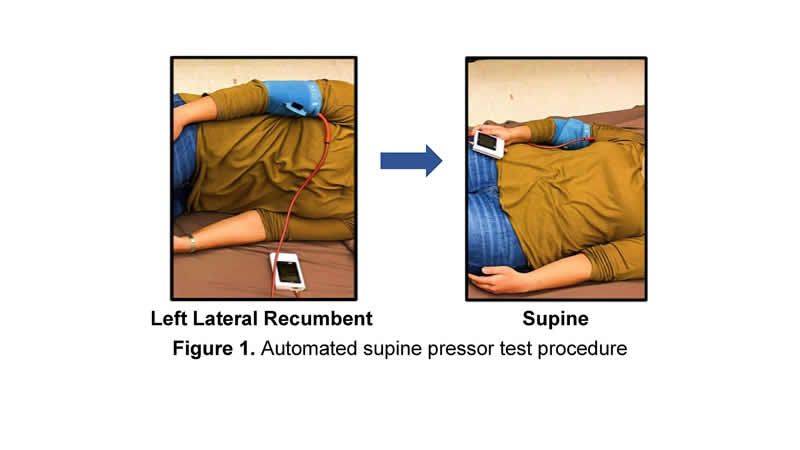

La conocida como prueba de presión supina se desarrolló hace décadas pero, eventualmente, se volvió poco común debido a las variaciones en la forma en la que los diferentes entidades sanitarias y médicos las efectuaban. Todas estas series de inconsistencias condujeron, irremediablemente, a resultados inexactos.

Al utilizar elementos como un teléfono inteligente, un acelerómetro y un manguito de presión arterial convencional, el sistema de prueba de presión del equipo de la Universidad de Purdue permite evaluaciones consistentes y reproducibles de los signos de preeclampsia.

La mujer que realiza la prueba por sí misma tiene que medir su presión arterial diastólica en diferentes posiciones y registrar la diferencia entre las lecturas. La aplicación que desarrolló el equipo del centro académico americano ayuda a guiar al usuario para que las lecturas sean precisas.